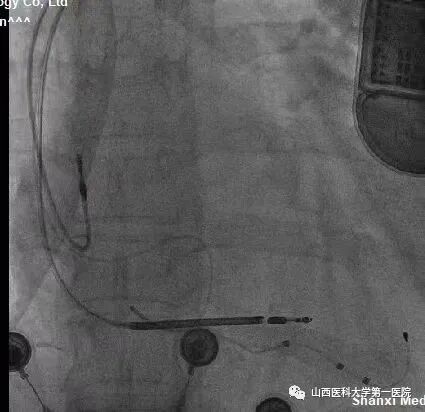

该患者冠状窦静脉侧支迂曲严重,前向无法进入左室侧静脉;同时,后静脉逆进入左室侧静脉的分支也非常迂曲,并且多处位置有膈神经刺激,左室电极多次调整,进入不同分支,并调整深度,最终寻找到起搏阈值好且无膈神经刺激位点。赵志强主任医师团队创造性的把冠脉PCI技术应用到手术中,并克服诸多困难,成功完成CRTD植入,期待患者后期心衰症状改善。